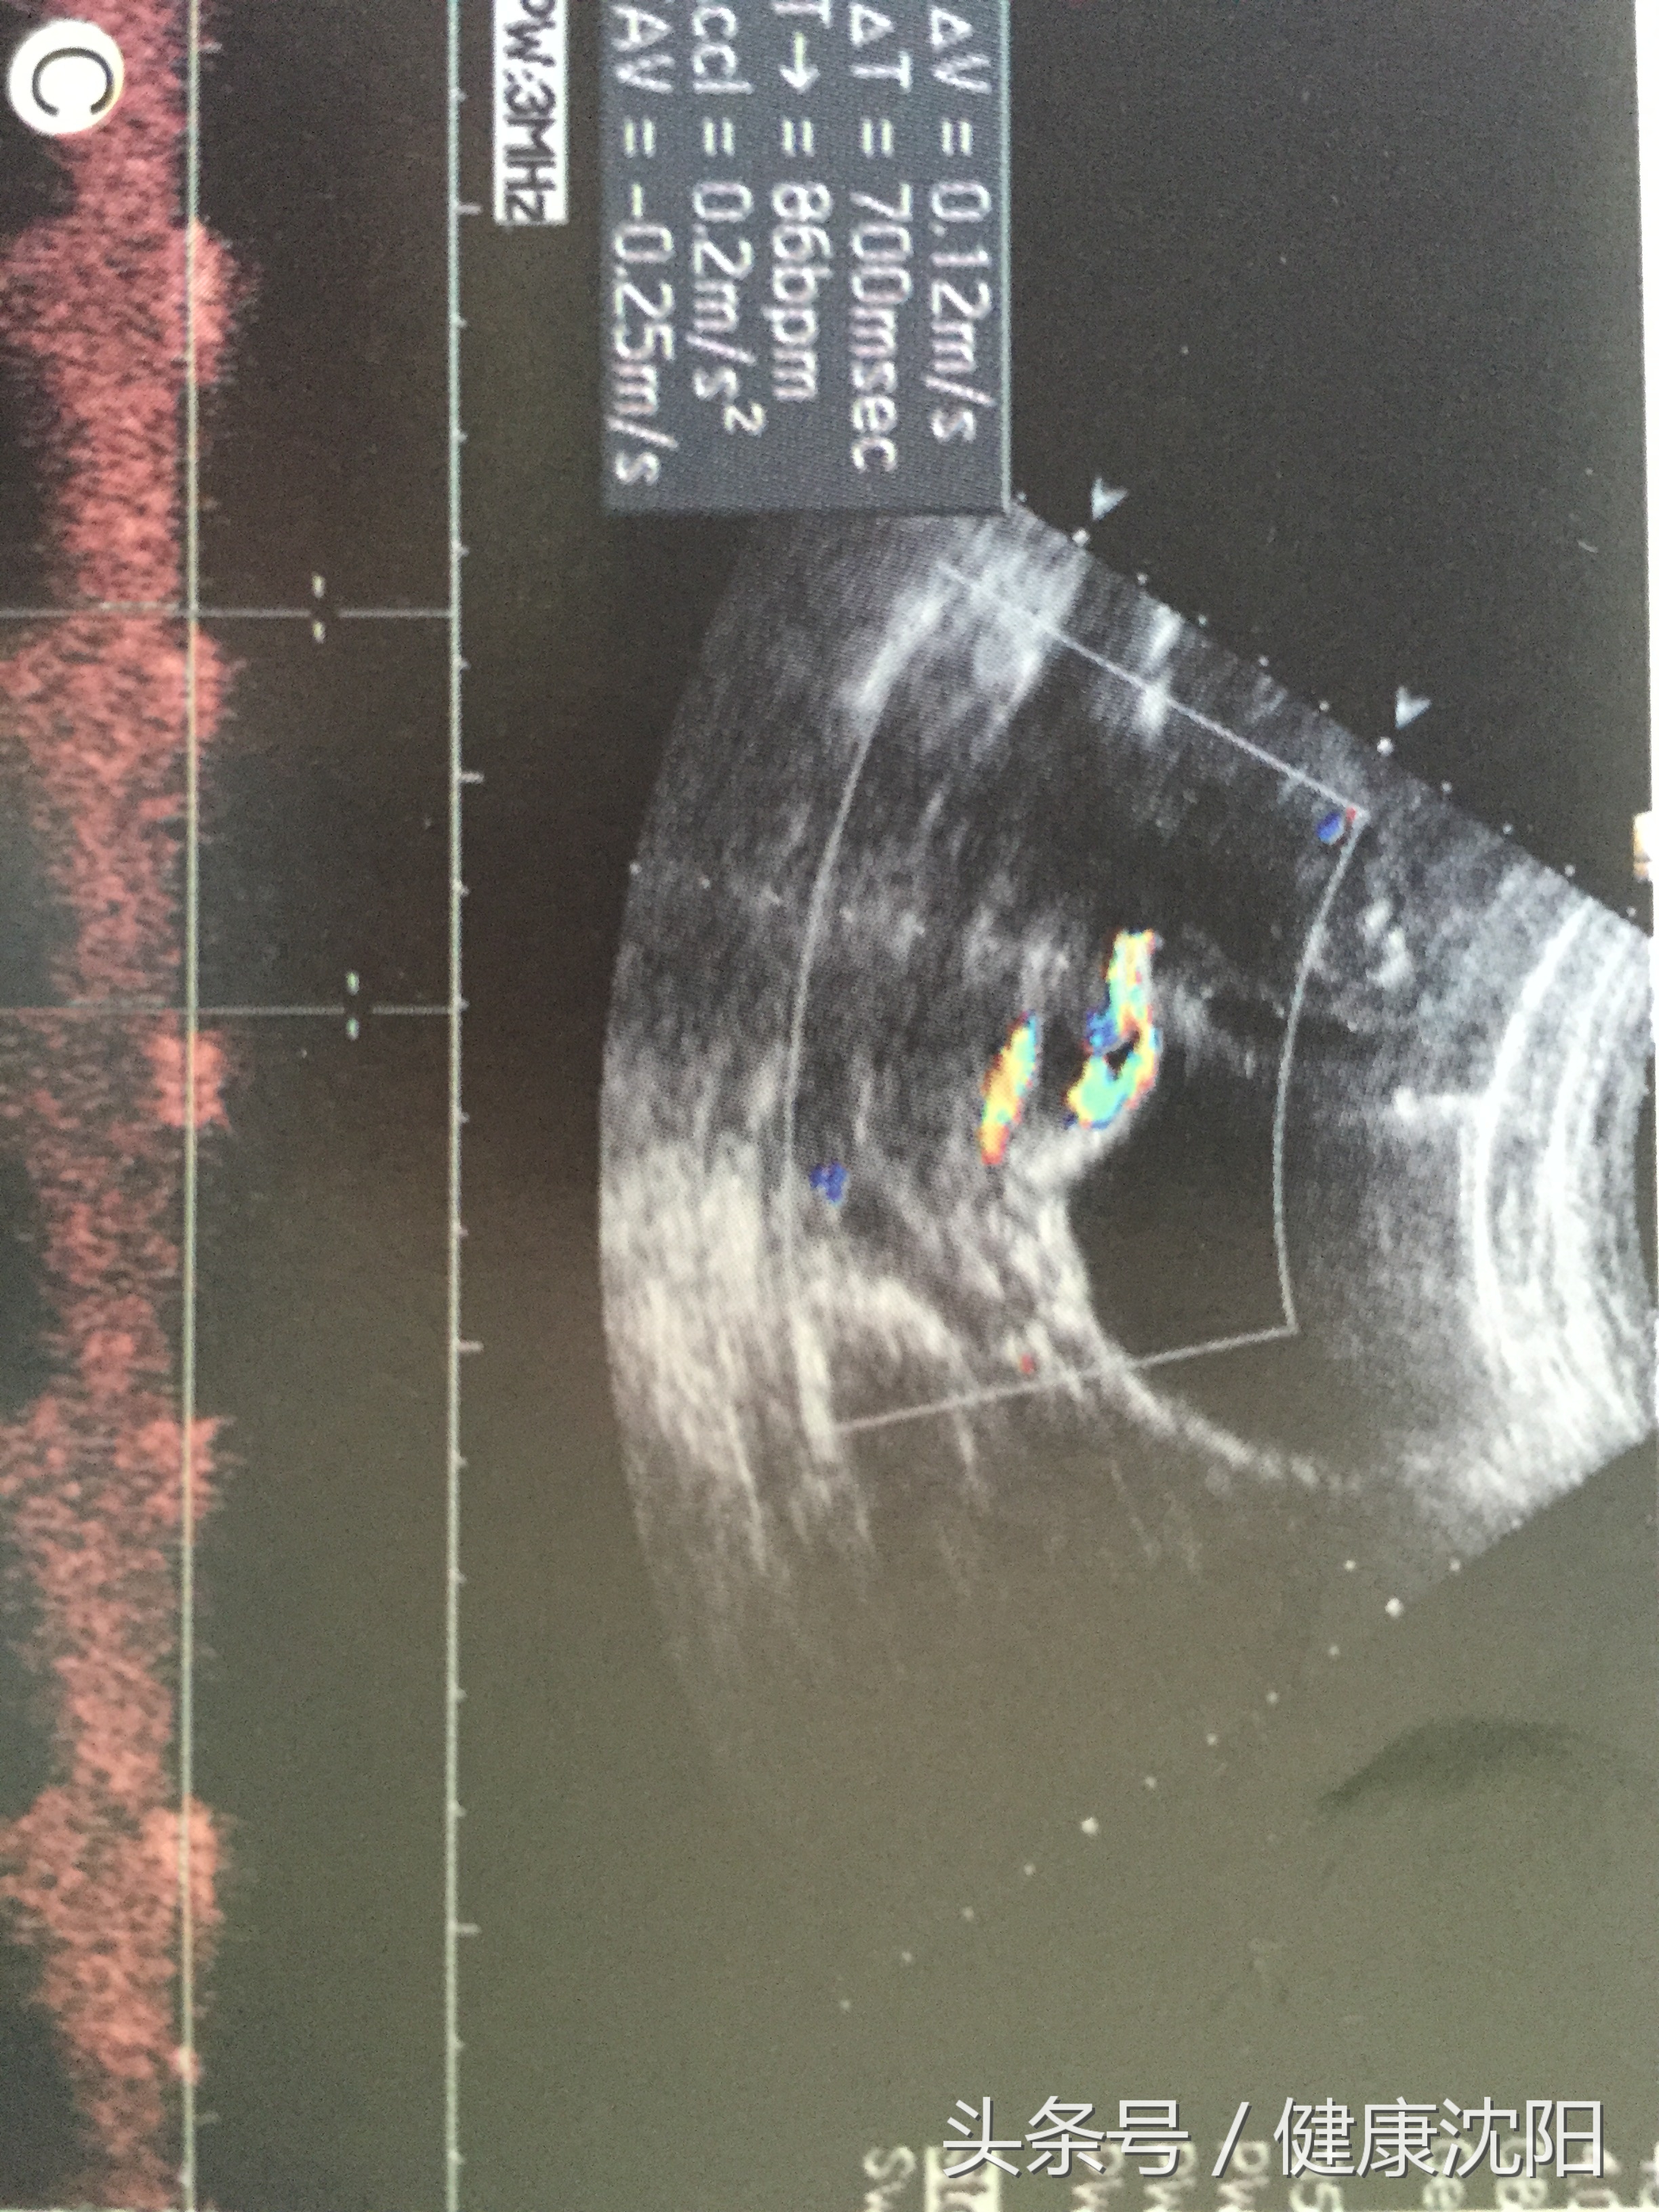

产前超声图像特征明显,表现为宫颈内口上方固定不变的条管状血管回声,呈单直条型或双直条型而缺乏螺旋,血管表面无Wharton胶包裹,或横跨宫颈内口,或接近宫颈内口,叠加CDFI亦可清晰显示宫颈内口上方的直条型血管,脉冲多普勒可探测到与胎儿心率一致的血管搏动。血管前置的产前诊断率与检查时孕周大小、检查者的经验有关。有研究表明,中孕期是诊断血管前置的较佳时间段。

二维超声显示位于宫颈之上的血管横切面呈多个圆形无回声,纵切面呈条形或曲线形无回声。

频谱多普勒或彩色多普勒对诊断血管前置极其有用,当疑宫颈内口有胎膜脐带血管时,彩色多普勒超声不仅可直接显示呈扇形分布的帆状脐带入口的胎膜血管或连接主副胎盘之间的胎膜血管,而且可获得典型的胎儿脐动脉频谱,故彩色多普勒超声可明确诊断血管前置。